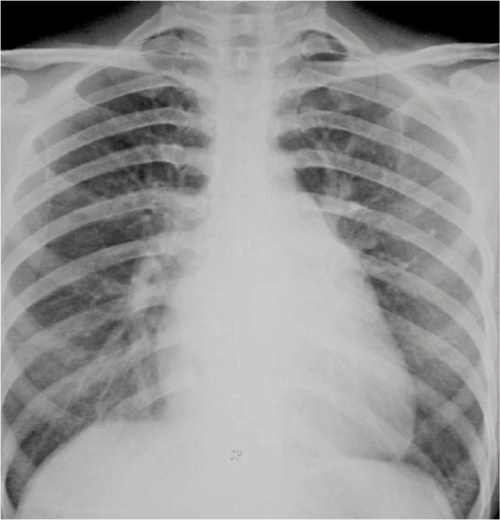

图2 胸片正位:梨形胸廓,心影增大

图2-22二尖瓣型心脏(梨型心)2.